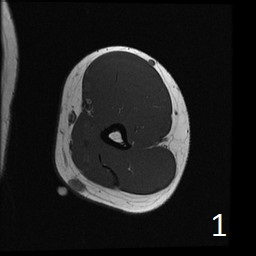

Angiolipoma is a subcutaneous benign tumor, made up of mature fat and blood vessels that often presents as multiple lesions. It sometimes arises intramuscularly. The incidence may be associated with familial heritage, close to 5% of the cases. Angiolipomas often arise in young patients, shortly before puberty, and are rarely seen in younger children or older adults. Angiolipomas often present as single or multiple subcutaneous tender to painful nodules (especially multiple ones). The pain may decrease as the lesion ages. No preference for ages or gender. Sites more commonly affected are the upper extremity and trunk, but rarely can affect head and neck region. MRI shows homogeneous and well circumscribed lesion, with intermediated signal on T1w (Fig. 1) and increased signal on T2W (Fig. 2). On fat suppress sequences the tumor may not suppress completely necause of its vascularity (Fig. 3). There is significant enhancement post contrast images (Fig. 4). On gross pathology the mass is a circumscribed, yellow-red nodular mass due high fat content and blood vessel proliferation. Microscopically, shows mature fat cells separated by branching network of small blood vessels, more prominent in subcapsular areas; there are usually associated fibrin thrombi (important sign). Adipocytes and interspersed vascular structures are seen, lined by elongated endothelial cells. These cells are irregular, and fingerlike extensions surrounded by periytes. Angiolipoma is a benign mass. It does not exhibit aggressive behavior. It rarely shows recurrence after resection. The treatment is complete surgical excision.

Fig. 1-4: Axial MRI of the arm shows a well circumscribed mass with intermediate signal on T1W (Fig. 1), and increased in T2W (Fig. 2). Fig. 3 Axial T1W FS shows a lesion and moderate intense on T1WFS post contrast (Fig. 4).